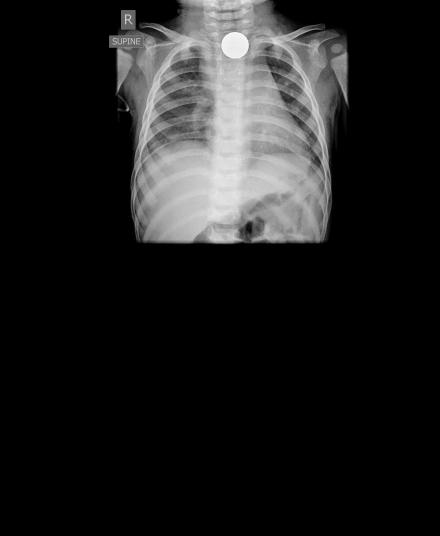

En av anledningarna till att axlarna åkt upp så mycket är nog röntgenbilderna. Det såg verkligen inte bra ut och det var inte svårt att förstå hur jobbigt det måste ha varit för stackars Morgan. Myntet ser verkligen stort ut i hans lilla kropp. Jag märker hur axlarna åker upp och andningen hamnar högre upp i bröstet på mig bara jag skriver om det. Ingen rolig känsla, så jag infogar bara bilderna så får ni själva fundera lite.

Nu är myntet ute och ligger alldeles svart i en liten platspåse (efter typ 3 veckor i Morgans matstrupe… 😦 och jag funderar på om vi skall sätta in det i en ram tillsammans med en printout av en röntgenbild, tillverka ett halsband av det eller göra något annat. I vilket fall skall vi spara det som en lycko-peng och en påminnelse om hur illa det kunde ha gått.